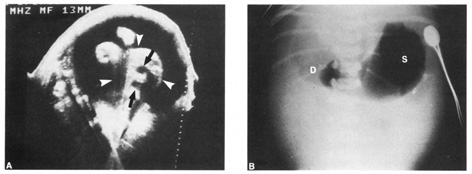

is also done to evaluate the fetal brain (Fig. 9), spine, stomach, heart, kidneys, placental location and assessment

comprehensive ultrasound are shown in Table 9. The ultrasound findings associated with Down syndrome include cardiac

defects or enlargement, cystic hygroma (Fig. 11), duodenal atresia (Fig. 12), omphalocele, polyhydramnios, choroids plexus cyst, and renal calyceal

Fig. 12. Duodenal atresia in a second trimester fetus. A: Ultrasound scan of fetal abdomen (arrowheads) showing two fluid-filled structures (arrows). Increased amniotic fluid (polyhydramnios) surrounds the

fetus. B: Newborn radiograph of upper abdomen demonstrating gas-filled stomach (S) and duodenum (D), which are typical findings of duodenal atresia. (Courtesy

of Alfred B. Kurtz, MD) Fig. 12. Duodenal atresia in a second trimester fetus. A: Ultrasound scan of fetal abdomen (arrowheads) showing two fluid-filled structures (arrows). Increased amniotic fluid (polyhydramnios) surrounds the

fetus. B: Newborn radiograph of upper abdomen demonstrating gas-filled stomach (S) and duodenum (D), which are typical findings of duodenal atresia. (Courtesy

of Alfred B. Kurtz, MD)

|